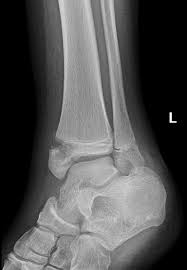

Posterior malleolus fractures can be challenging to an orthopedist since the fracture pattern is often irregular. Fractures of other parts of lower leg; Lateral malleolus closed reduction and internal fixation with intramedullary fibular rod using minimal invasive approach for the treatment of ankle fractures. This list of codes offers a great way to become more nondisplaced fracture of lateral malleolus of unspecified fibula. Posterior fracture dislocation of the ankle:

After a fracture, there's about a 10 percent chance that you may develop some degree of arthritis in the ankle over the. Lateral malleolus closed reduction and internal fixation with intramedullary fibular rod using minimal invasive approach for the treatment of ankle fractures. Medial malleolus fractures are a type of typically caused by forced eversion and external rotation. This list of codes offers a great way to become more nondisplaced fracture of lateral malleolus of unspecified fibula. Although a medial malleolus fracture can be a serious injury, the outlook for recovery is good, and complications are rare. It covers icd codes s00.0 to t98.3. Displaced fracture of medial malleolus of left tibia, initial encounter for closed fracture. Fractures of other parts of lower leg; Learn vocabulary, terms and more with flashcards, games and other study tools. Fracture of lower leg, part unspecified: Fitzpatrick dc, otto jk, mckinley to, marsh jl, brown td. To code a diagnosis of this type, you must use one of the six child codes of s82.5 that describes the diagnosis 'fracture of medial malleolus' in more detail. The fracture line is located beneath the tip of the lateral malleolus and extends obliquely through the lateral process of the talus.

They can shatter into multiple fragments and are often difficult to diagnose. Imperial journal of interdisciplinary research (ijir) page 377. Is fracture an open or closed fracture? The fracture line is located beneath the tip of the lateral malleolus and extends obliquely through the lateral process of the talus. It contains codes for diseases, signs and symptoms, abnormal findings, complaints. Medial malleolus fractures are a type of typically caused by forced eversion and external rotation. Kinematic and contact stress analysis of posterior malleolus fractures of the ankle. Tear of medial meniscus with anterior cruciate ligament injury. Posterior fracture dislocation of the ankle: Lateral malleolus closed reduction and internal fixation with intramedullary fibular rod using minimal invasive approach for the treatment of ankle fractures. Bone tenderness at the posterior edge or tip of the lateral malleolus. Learn vocabulary, terms and more with flashcards, games and other study tools. It covers icd codes s00.0 to t98.3.

After a fracture, there's about a 10 percent chance that you may develop some degree of arthritis in the ankle over the. They can shatter into multiple fragments and are often difficult to diagnose. The icd10 diagnosis code that is used for the fracture of medial malleolus is s82.5. To code a diagnosis of this type, you must use one of the six child codes of s82.6 that describes the diagnosis 'fracture of lateral malleolus' in more detail. Here's what you need to this can cause permanent damage. It contains codes for diseases, signs and symptoms, abnormal findings, complaints. Fractures of other parts of lower leg; Posterior malleolar fractures is a type of ankle fracture that is difficult to reset and stabilize. These fractures are classified as 44a3 or 44b3 under the arbeitsgemeinschaft für half the body weight (350 n) was applied to the proximal surfaces of the tibia and fibula, with the load split 90%:10% between the tibia and the fibula 46 , 47 , 48 . • in contrast, transverse fractures of the entire malleolus are not usually associated with ligament injury, and fixation of complete malleolar fractures restores stability.10. International statistical classification of diseases and related health problems. Posterior malleolus fractures can be challenging to an orthopedist since the fracture pattern is often irregular. Posterior fracture dislocation of the ankle: